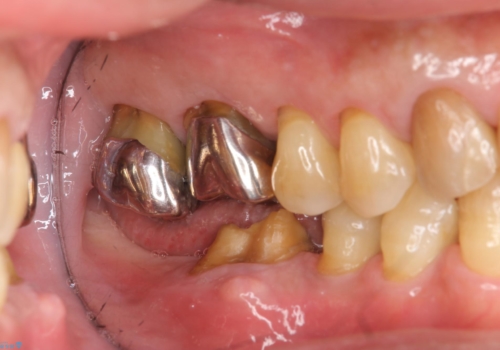

- 右下の奥歯が割れてしまい、抜歯を行いました。

ブリッジにできない位置であったため、インプラントでかめるようにしました。

また、向かい合う上の歯が挺出(伸び出してしまうこと)しており、インプラントを入れることが難しかったため、長さを短くかぶせ治しました。